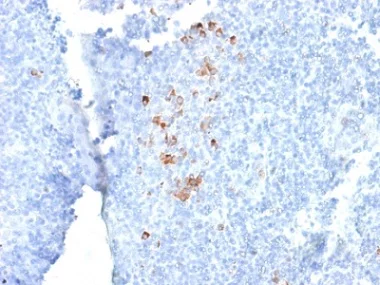

Immunohistochemistry (Formalin/PFA-fixed paraffin-embedded sections) - Anti-IgG antibody [rIG266] (AB238004)

Formalin-fixed, paraffin-embedded human tonsil tissue stained for IgG using ab238004 at 1 μg/ml in immunohistochemical analysis.